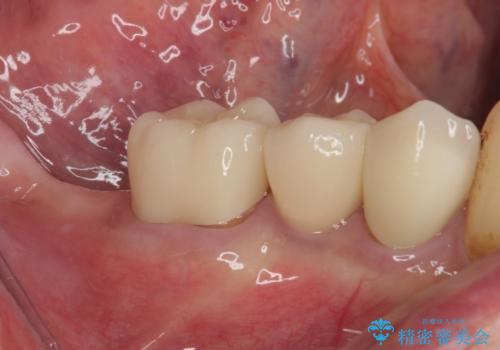

破折してしまった奥歯 抜歯即時埋入で短期間インプラント治療

- 奥歯に装着していたクラウンが外れてしまったとのことで来院された患者様です。

診察したところ、歯根に破折線が確認され抜歯が必要な状態でした。

歯肉や歯槽骨の状態は良好であったため、抜歯即時埋入インプラントによる補綴治療を行うこととしました。

抜歯、インプラント埋入、仮歯の装着を1度に行うことができ、治療終了までわずか3か月で終えることができました。